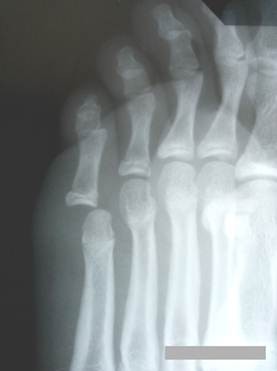

Эпифизарная

клинодактилия 2-го пальца стопы с поражением головки средней фаланги у мальчика

16 лет. На рентгенографии, кроме того, определяется вальгусное положение

большого пальца. Однако же, о поперечном плоскостопии с Hallux Valgus

речь не идет ввиду отсутствия клинических проявлений: боли, отека, кожного

намина. Лечение не обязательно. При

желании больного можно выполнить неэкономную (с удалением костной ткани)

клиновидную остеотомию средней фаланги со стороны большого пальца. При закрытии

клиновидного дефекта палец выпрямится. Последующий остеосинтез фаланги

выполняется тонкими спицами трансоссально или перекрестно. Второй вариант операции – резекция головки средней фаланги с последующей

спицевой фиксацией дистальной фаланги в правильном положении – не

представляется более оптимальным.